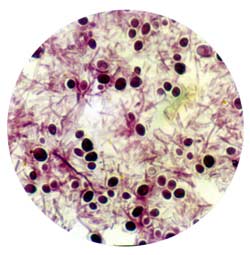

Чаще зигомицеты определяют при микроскопии исследуемых субстратов, реже - при посеве. Возбудитель очень редко выделяют в посевах крови даже при диссеминированном зигомикозе. Поэтому именно микроскопия материала из очагов поражения с окраской калькофлуором белым или специфическими методами является основным методом ранней диагностики зигомикоза. При этом выявляют характерный широкий (10-50 мкм) несептированный или редкосептированный мицелий, ветвящийся под прямым углом. Однако в связи с низкой диагностической значимостью микроскопии и посева аспирата из носа, мокроты и БАЛ, нередко необходимо повторное исследование. Следует отметить, что хранение материала в холодильнике, гомогенизация его перед посевом и т.д. также могут уменьшать вероятность выделения зигомицетов в культуре.